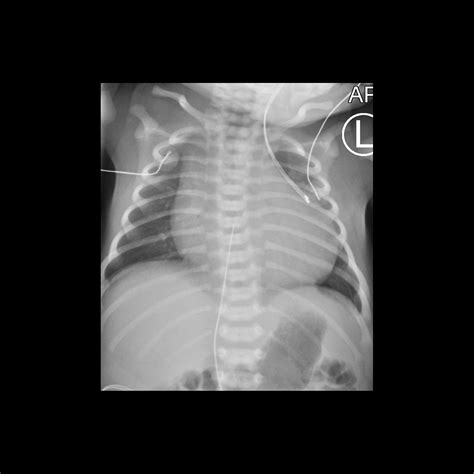

• X-rays: Often the first line of defense for bone fractures or lung issues.

X-ray Minimal Bone fractures, pneumonia, chest congestion